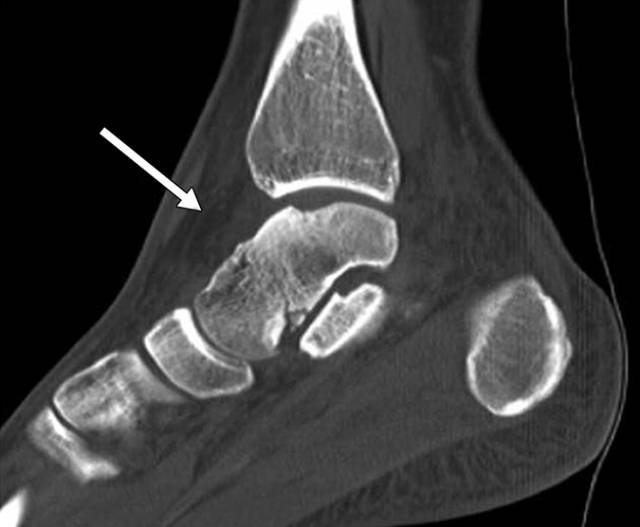

图5 -53岁男性骨折骨折。C,随后的矢状(C)和轴向(D)CT图像更全面地显示通过延伸到距下关节的距骨的身体的另外的倾斜骨折(箭头)。

图 6-35岁的女人,脚后疼痛。A,在X光片,包括侧位片,骨折很难看到,甚至在事后。B,在这个矢状面CT重建中观察到第四跖关节(箭头)处的立方体的关节内骨折。